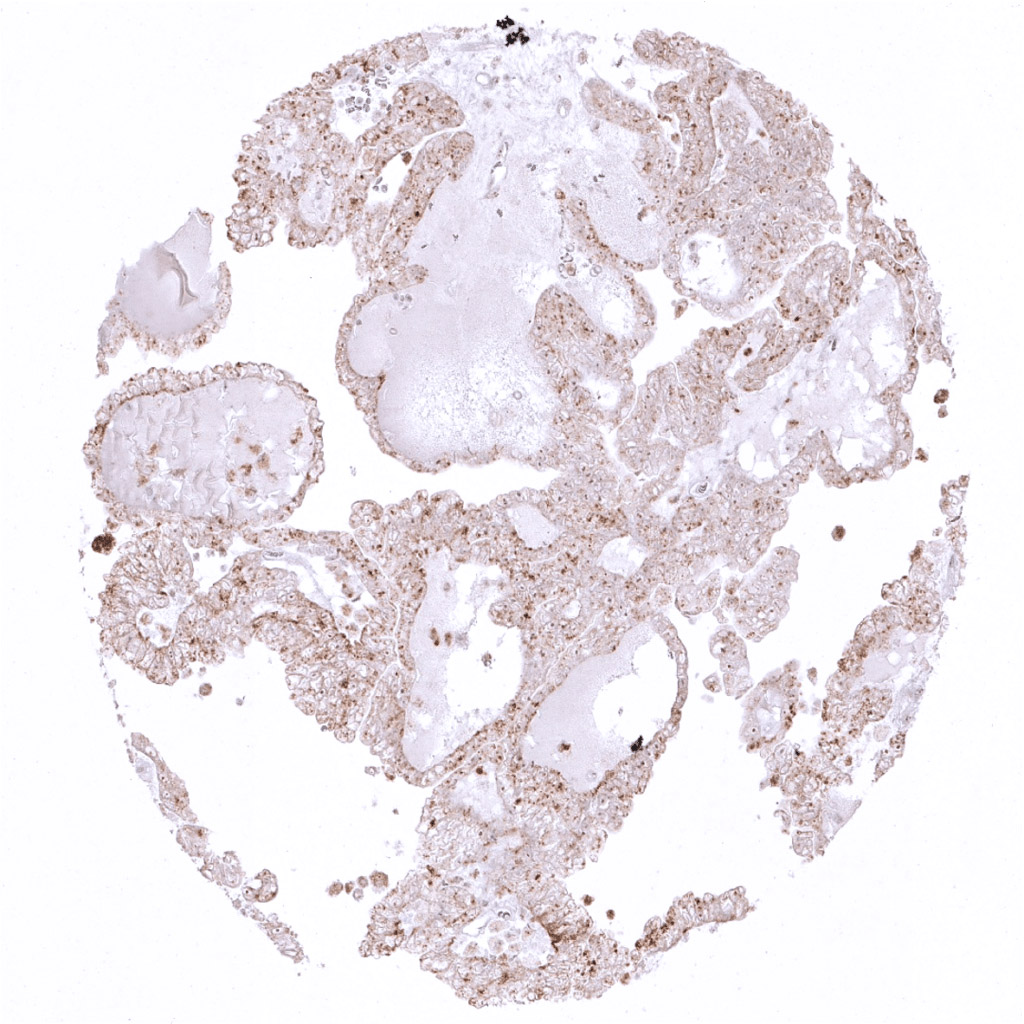

Ovary- Strong Napsin A immunostaining in a clear cell carcinoma of the ovary.

Uterus- Malignant mixed Mullerian tumor with moderate Napsin A immunostaining in glandular tumor cells.

Uterus- Moderate Napsin A immunostaining in a serous endometrium carcinoma.

Uterus- Strong Napsin A immunostain in a malignant mixed Mullerian tumor of the uterus. Epithelial tumor cells are predominantly affected.